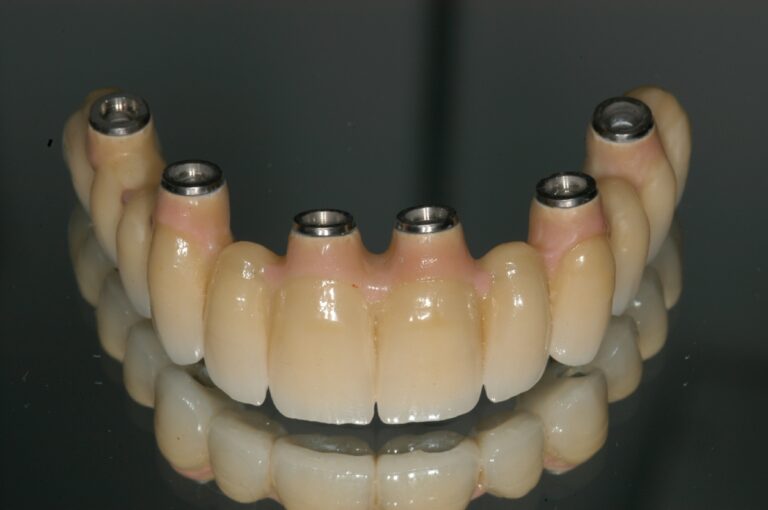

Following improvements to the surfaces of our implants, and utilising experience gained over many years, we can now offer you “FIXED TEETH TODAY”. In most cases, we are able to place a fixed bridge onto the implants immediately after placement. You would therefore arrive at the surgery with loose dentures, and leave with a number of implants placed and a FIXED bridge fitted onto them. This concept reduces the discomfort and healing time following implant placement, and provides immediate satisfaction to our patients. Imagine being able to bite into an apple again for the first time in many years!